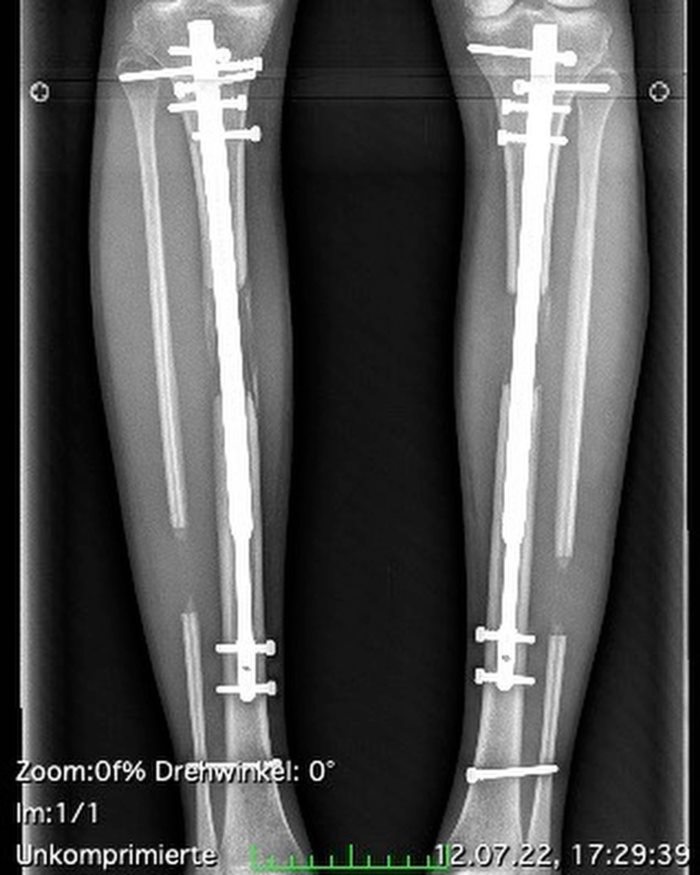

ย้อนกลับไปเมื่อตอนที่เทเรเซีย อายุ 24 ปี เธอเป็นนางแบบสาวที่รู้จักจากรายการเรียลลิตี้ German Celebrity Big Brother ในขณะนั้นสูง 5 ฟุต 6 นิ้ว หรือประมาณ 167 เซนติเมตร ก่อนที่เธอจะตัดสินใจจ่ายเงินจำนวนมากกว่า 130,000 ปอนด์ (ราว 5.7 ล้านบาท) เพื่อเข้ารับการผ่าตัดที่ไม่ปกติ นั่นคือการยืดขาต่อความยาว เพื่อให้ส่วนสูงของเธอเพิ่มขึ้นมา 5.5 นิ้ว หรือประมาณ 14 เซนติเมตร

นอกจากนี้ เธอยังเล่าถึงความเจ็บปวดของการผ่าตัด ว่า กระดูกหน้าแข้งของเธอหักหมด และกล้ามเนื้อน่องก็แตก จากการสอดแท่งยืดเข้าไป และทุกวันเธอจะต้องคอยยืดขาส่วนล่าง จับเข่าด้วยมือข้างหนึ่ง ส่วนมืออีกข้างจับเท้าดึงเข้าด้านในจนกว่าจะได้ยินเสียงดังกริ๊ก แต่ละวันเธอต้องทำทั้งสองข้าง ในแต่ละข้างจะต้องได้ยินทั้งหมด 10 กริ๊ก เท่ากับความสูงที่จะได้เพิ่มขึ้นมา 0.5 มิลลิเมตร